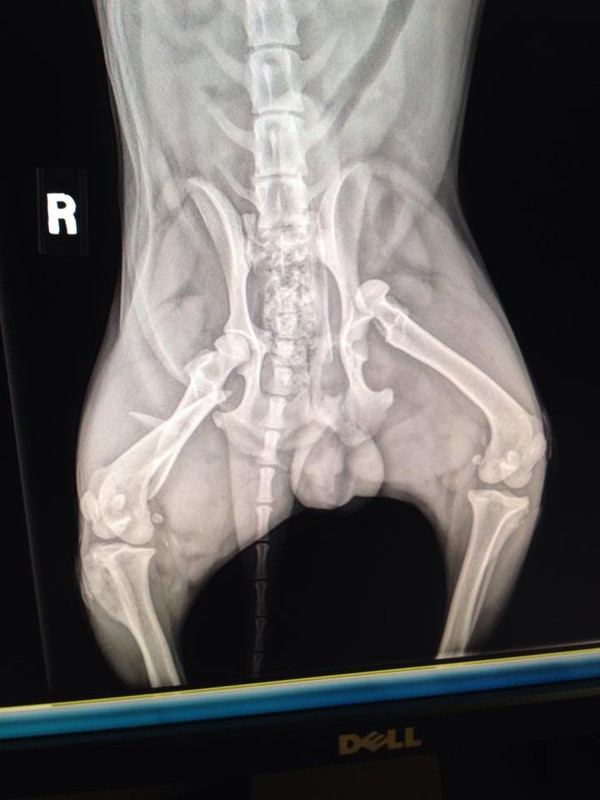

Jacob's Leg Injury

X-Ray Image of Multiple Breaks

for treatment. It was determined he had suffered a broken pelvis

and both rear leg from the hit. injuries will require surgery to